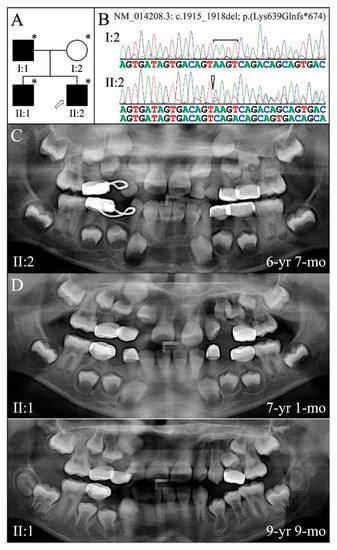

| 5 | g.11049_11052delAAGT | c.1915_1918delAAGT | p.(Lys639Glnfs*674) | Family 5 [82] |

| 5 | Illumina HiSeq 2500 (WES) | NG_011595.1:g.11049_11052delAAGT; NM_014208.3:c.1915_1918delAAGT; NP_055023.2: p.(Lys639Glnfs*674) | −1 Frameshift | I:1, affected father: 233.91× I:2, unaffected mother: 165.19× II:2, affected 2nd child: 178.45× |